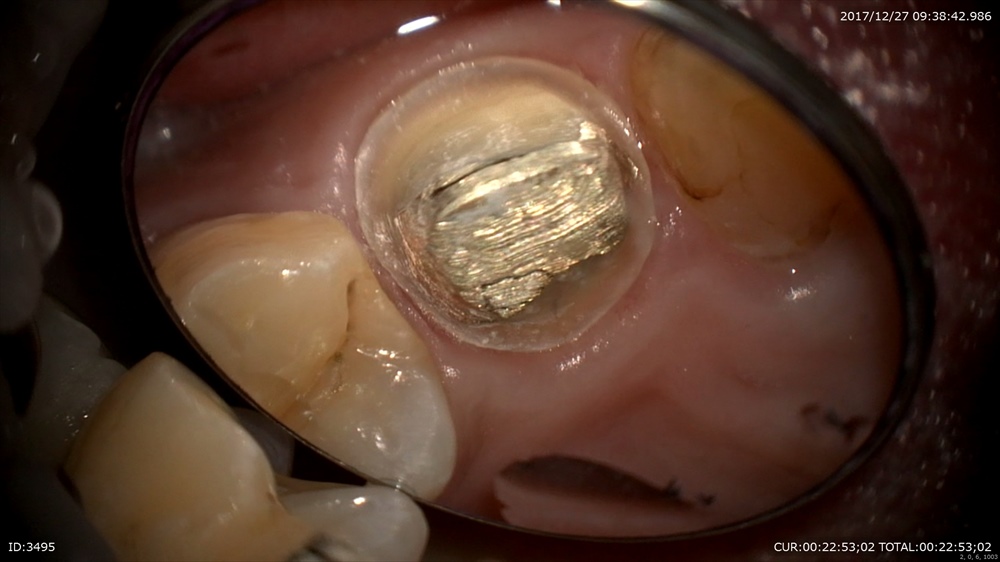

次の患者さまは精密根管治療

ラバーダムで準備

結構汚れています

綺麗にします。根管内の細菌がぐっと減りました。